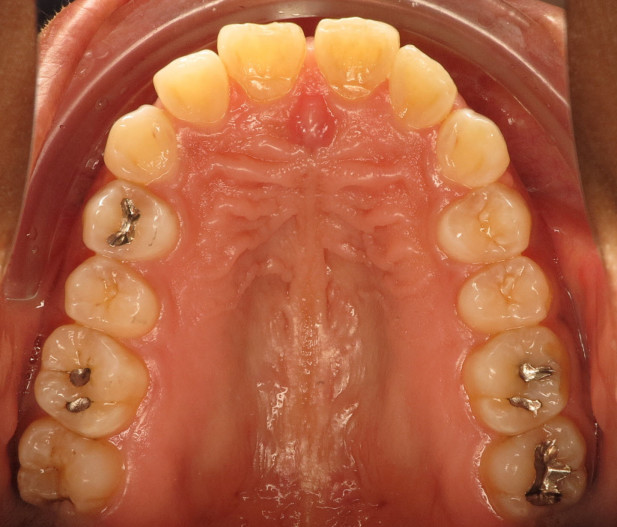

Der intraorale Befund (Abb. 2a–e) sowie die Modellanalyse (Abb. 3a–e) zeigten neben dem Diastema mediale im Oberkiefer vor allen Dingen eine Anteinklination und Supraokklusion beider Fronten. Besonders anterior wiesen beide Zahnbögen eine transversale Enge auf. Dies zeigte sich in einem deutlichen Unterkieferfrontengstand mit Labialkippung des Zahnes 41. Neben Abrasionen und Schlifffacetten, vor allem in der Front, waren auch vereinzelt Gingivarezessionen erkennbar. An Zahn 11 lag eine Schmelzfraktur der Inzisalkante vor. Durch die zwangsgeführte Laterognathie ergab sich eine Mittellinienverschiebung nach rechts von 3 mm. Eine beidseitige Distalokklusion bei vergrößerter sagittaler (6 mm) und vertikaler (5 mm) Stufe war erkennbar. Aufgrund der deutlichen transversalen Zahnbogenenge im Unterkiefer ergab sich links eine Tendenz zum Scherenbiss.